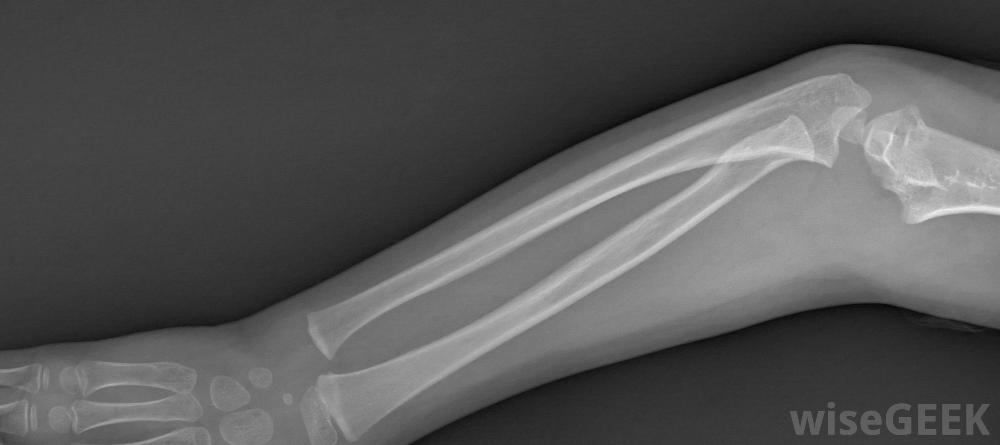

糖钳夹板在前臂骨折中很常见对于需要保护手臂不受电击的损伤,最好的前臂夹板可能是充气的。空气垫通常会将夹板塑造成四肢的轮廓。它还对前臂施加均匀的压力,保持血液循环,另一个优点是前臂空气夹板通常是透明的,这意味着在接受x光检查时可以不使用。但是,它可能会被锋利的物体弹出,而且空气夹板并不总能提供最好的通风

网球肘患者可能会从气夹板中获益。如果手臂骨折,你可能会得到掌侧夹板或糖钳夹板。夹板通常非常坚硬,由铝、塑料或玻璃纤维制成,并有一个坚硬的金属片来稳定。这些类型的夹板通常从手掌开始,沿着前臂向上,在到达肘部之前停止